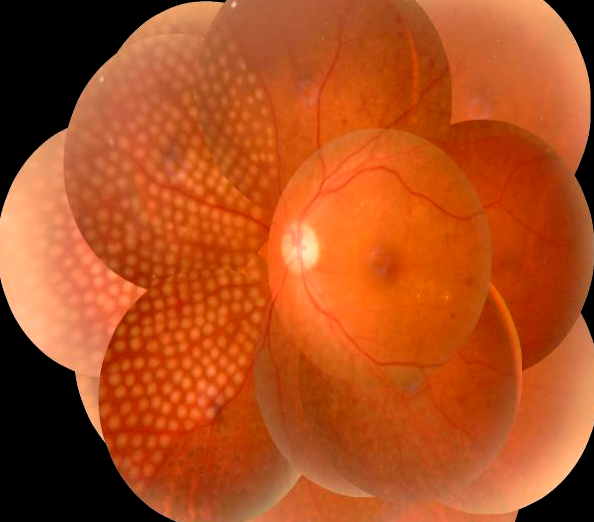

近年来,随着高血压、糖尿病、高血脂等患者的增多,这些疾病导致的视网膜静脉阻塞、糖尿病视网膜病变、黄斑水肿等眼底并发症的发病率有逐年增高的趋势。我院眼科在临床治疗工作中,发现患有眼底疾病的患者明显增多,而这些眼底疾病需要早筛查、早发现、早治疗,如果等到晚期出现视网膜脱离等严重并发症,等待患者的将是永久的失明。

视网膜激光光凝术是治疗眼底疾病的主要方法。利用激光的热效应,作用于眼底的病变部位,使之被光凝破坏形成瘢痕,从而达到封闭或破坏缺氧区的治疗技术,可以有效地控制视网膜细胞的代谢,减少视网膜水肿渗出、减轻黄斑水肿、改善视网膜供氧、抑制新生血管形成,阻止视网膜病变的进展,防止视网膜遭到进一步的损害。

常用于糖尿病视网膜病变、视网膜静脉阻塞、视网膜血管炎、视网膜血管瘤、中心性浆液性脉络膜视网膜病变、外层渗出性视网膜病变、家族性渗出性视网膜病变、早产儿视网膜病变、视网膜裂孔、视网膜变性等。